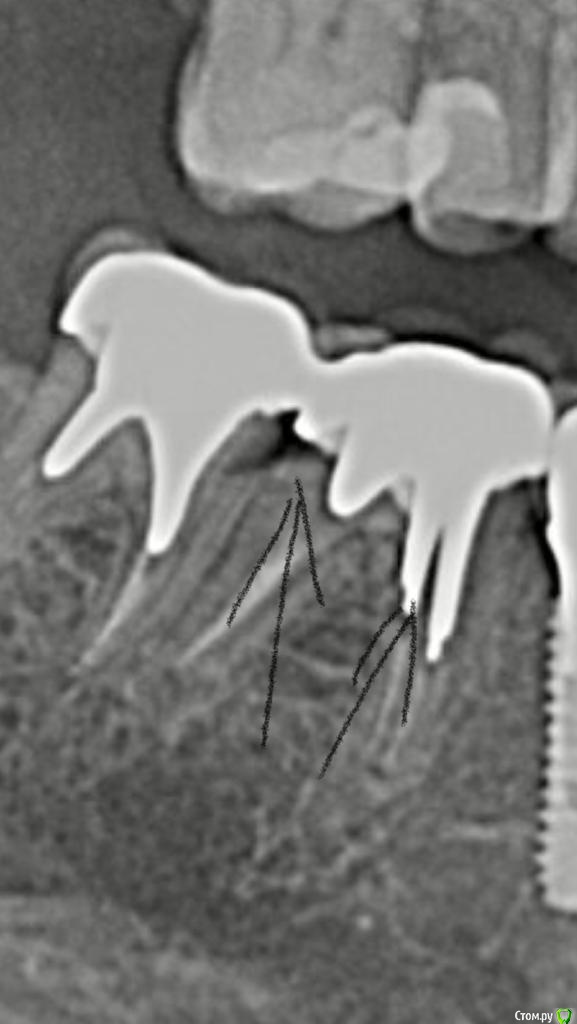

Туманская Опубликовано 5 октября, 2018 Автор Поделиться Опубликовано 5 октября, 2018 Панорамный снимок Ссылка на комментарий

Туманская Опубликовано 5 октября, 2018 Автор Поделиться Опубликовано 5 октября, 2018 Если не сложно, посмотрите, пожалуйста на зубы под коронками. Одон врач говорит, что все норм. Другой, что на 46м прилегание вкладки плохое и надо переделывать. Первый говорит, что убрать вкладку в моем случае не получится, потеряю зуб. При этом у меня есть боли неясные где-то в районе этих зубов, но точно определить не могу. Ставить новые коронки, если там не все гладко, тоже не хочется. Когда сняли старые, между зубами оказалась пролежень. Что делать дальше? Вкладки серебряные. Ссылка на комментарий

Дмитрий Л. Опубликовано 7 октября, 2018 Поделиться Опубликовано 7 октября, 2018 Если не сложно, посмотрите, пожалуйста на зубы под коронками. Одон врач говорит, что все норм. Другой, что на 46м прилегание вкладки плохое и надо переделывать. Первый говорит, что убрать вкладку в моем случае не получится, потеряю зуб. При этом у меня есть боли неясные где-то в районе этих зубов, но точно определить не могу. Ставить новые коронки, если там не все гладко, тоже не хочется. Когда сняли старые, между зубами оказалась пролежень. Что делать дальше? Вкладки серебряные.Кариес корня под вкладками. Пародонтальный карман и отсюда боли (дискомфорт).Надо переделать, но то, что зубы можно потерять от этой переделки, тоже правда. Решать вам.По поводу гальваноза от серебра: всё возможно, любые металлы могут создать гальваноз. Смотрите по самочувствию.Аллерготесты я бы не делал, лишняя трата времени и денег. Делайте из циркония. Ссылка на комментарий